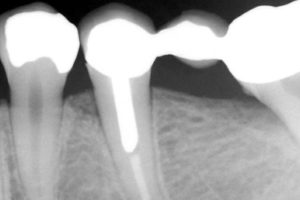

Le nostre apparecchiature diagnostiche sono minimamente invasive. Per le videoradiografie usiamo sensori di ultima generazione che evitano lo sviluppo di lastre fotografiche riducendo del 90% l’emissione di raggi X necessari per l’esame.

L’esame viene eseguito in maniera istantanea. I vantaggi sono particolarmente utili nel caso di pazienti giovani e bambini e donne in stato di gravidanza. In questi soggetti prima dell’avvento della videoradiografia era controindicato fare esami di questo tipo. Con l’RVG, invece, dato il bassissimo rischio radiogeno, è il medico a decidere l’opportunità di eseguire l’esame, che spesso rappresenta un vantaggio e non un pericolo.